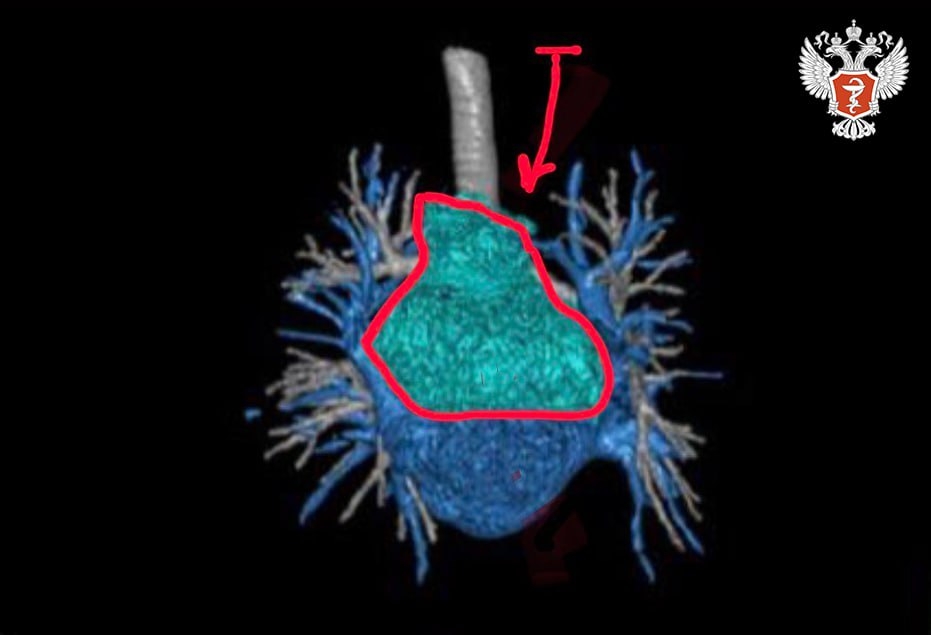

48-летняя пациентка обратилась в НМИЦ онкологии им. Н.Н. Блохина Минздрава России с диагнозом «параганглиома сердца». Опухоль поражала левое предсердие.

➡ Специалисты выяснили, что удалить опухоль стандартным способом с использованием бычьего ксеноперикарда невозможно.

Врачи решили провести аутотрансплантацию сердца — высокотехнологическую операцию, при которой орган пациента на время извлекают из грудной полости для удаления труднодоступной опухоли, а затем возвращают на место.